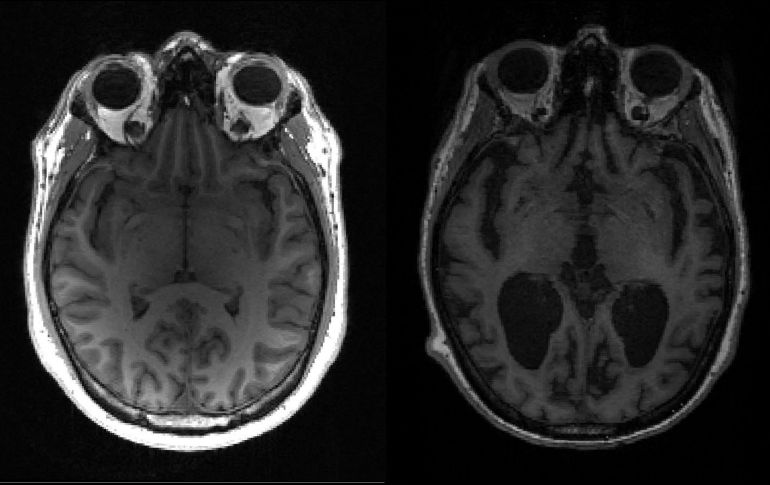

Grupos de proteínas tóxicas que se cree que son responsables del deterioro cognitivo asociado con la enfermedad de Alzheimer llegan tempranamente a diferentes regiones del cerebro y luego se acumulan durante décadas, según un nuevo estudio publicado el viernes.

En la enfermedad de Alzheimer, tau y otra proteína llamada beta amiloide se acumulan en nudos y placas -conocidos ambos como agregados- que matan las células cerebrales y encogen el cerebro.

Esto, a su vez, se traduce en pérdida de memoria, cambios de personalidad e incapacidad para realizar funciones cotidianas. Se estima que 44 millones de personas padecen la enfermedad en todo el mundo.

El grado de la enfermedad de Alzheimer se mide según la denominada "Escala Braak". El equipo encontró que lleva unos 35 años avanzar desde la etapa tres, cuando comienzan a aparecer síntomas leves, a la etapa seis, que es la más avanzada.

Si los agregados se duplican aproximadamente en cinco años, entonces en 35 años se habrían multiplicado por 128. Ese crecimiento exponencial "explica porqué la enfermedad demora tanto en desarrollarse y luego la persona se deteriora rápidamente".